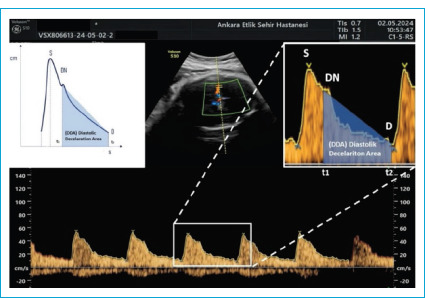

Objectives: This study aimed to assess the predictive value of the Diastolic Deceleration Area (DDA), a novel Doppler ultrasound parameter, in detecting adverse neonatal outcomes in fetuses with late-onset fetal growth restriction (FGR). While Doppler parameters such as cerebroplacental ratio (CPR), umbilicocerebral ratio (UCR), and cerebralplacentaluterine ratio (CPUR) are commonly used for fetal monitoring, their predictive power varies. Given the importance of cerebral blood flow redistribution in fetal adaptation to hypoxia, we investigated whether DDA could serve as a reliable indicator of fetal distress and adverse perinatal outcomes.

Methods: This prospective case-control study was conducted between January 2024 and July 2024, including 90 pregnant women: 45 diagnosed with late-onset FGR and 45 gestational age-matched healthy controls. Doppler ultrasound measurements, including umbilical artery, uterine artery, middle cerebral artery Doppler indices, CPR, UCR, CPUR, and DDA, were performed. The primary outcome was the prediction of adverse neonatal events, such as neonatal intensive care unit (NICU) admission, neonatal sepsis, respiratory distress, low APGAR scores, and low cord blood pH. Receiver Operating Characteristic (ROC) curve analysis was used to determine the predictive ability of the Doppler indices.

Results: DDA values were significantly higher in the FGR group compared to controls (p<0.001). At a cut-off value of >7.23, DDA demonstrated 50% sensitivity and 88% specificity, making it the most specific Doppler parameter for predicting adverse neonatal outcomes. In comparison, CPR (cut-off ≤2.11), UCR (cut-off >0.46) and CPUR (cut-off ≤1.36) had higher sensitivity (96%, 96%, 54%) but lower specificity (32%, 31% and 85% respectively).

Conclusion: DDA is a promising Doppler parameter for identifying fetuses at risk in late-onset FGR. Its high specificity suggests it could be a valuable supplementary tool alongside traditional Doppler indices for better risk assessment and clinical decision-making. Further studies are needed to validate its role in perinatal care.